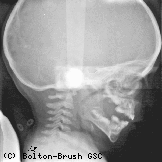

The Bolton Study, concentrating on growth and development of the face and teeth, was initiated in 1929 by B. Holly Broadbent, Sr. The radiograph was the primary tool used by these researchers to study the physical changes that occurred in the bones of the body with time. Over the years, radiographs were taken of the same individuals on an annual basis for the purpose of determining how the body grows. Between the two collections, there were over 6,000 research subjects with over 2,800 of those subjects participating in both studies.

In 1970, under the direction of Dr. B. Holly Broadbent Jr., the Brush Inquiry and Bolton Study collections combined to form the Bolton-Brush Growth Study Center, which is housed at the Case Western Reserve University School of Dental Medicine. The Bolton-Brush Center houses more than 200,000 radiographs of the head (lateral and frontal views) and the major joints of the body (shoulder, elbow, wrist/hand, pelvis, knee, and ankle/foot).

X-ray of a child's head